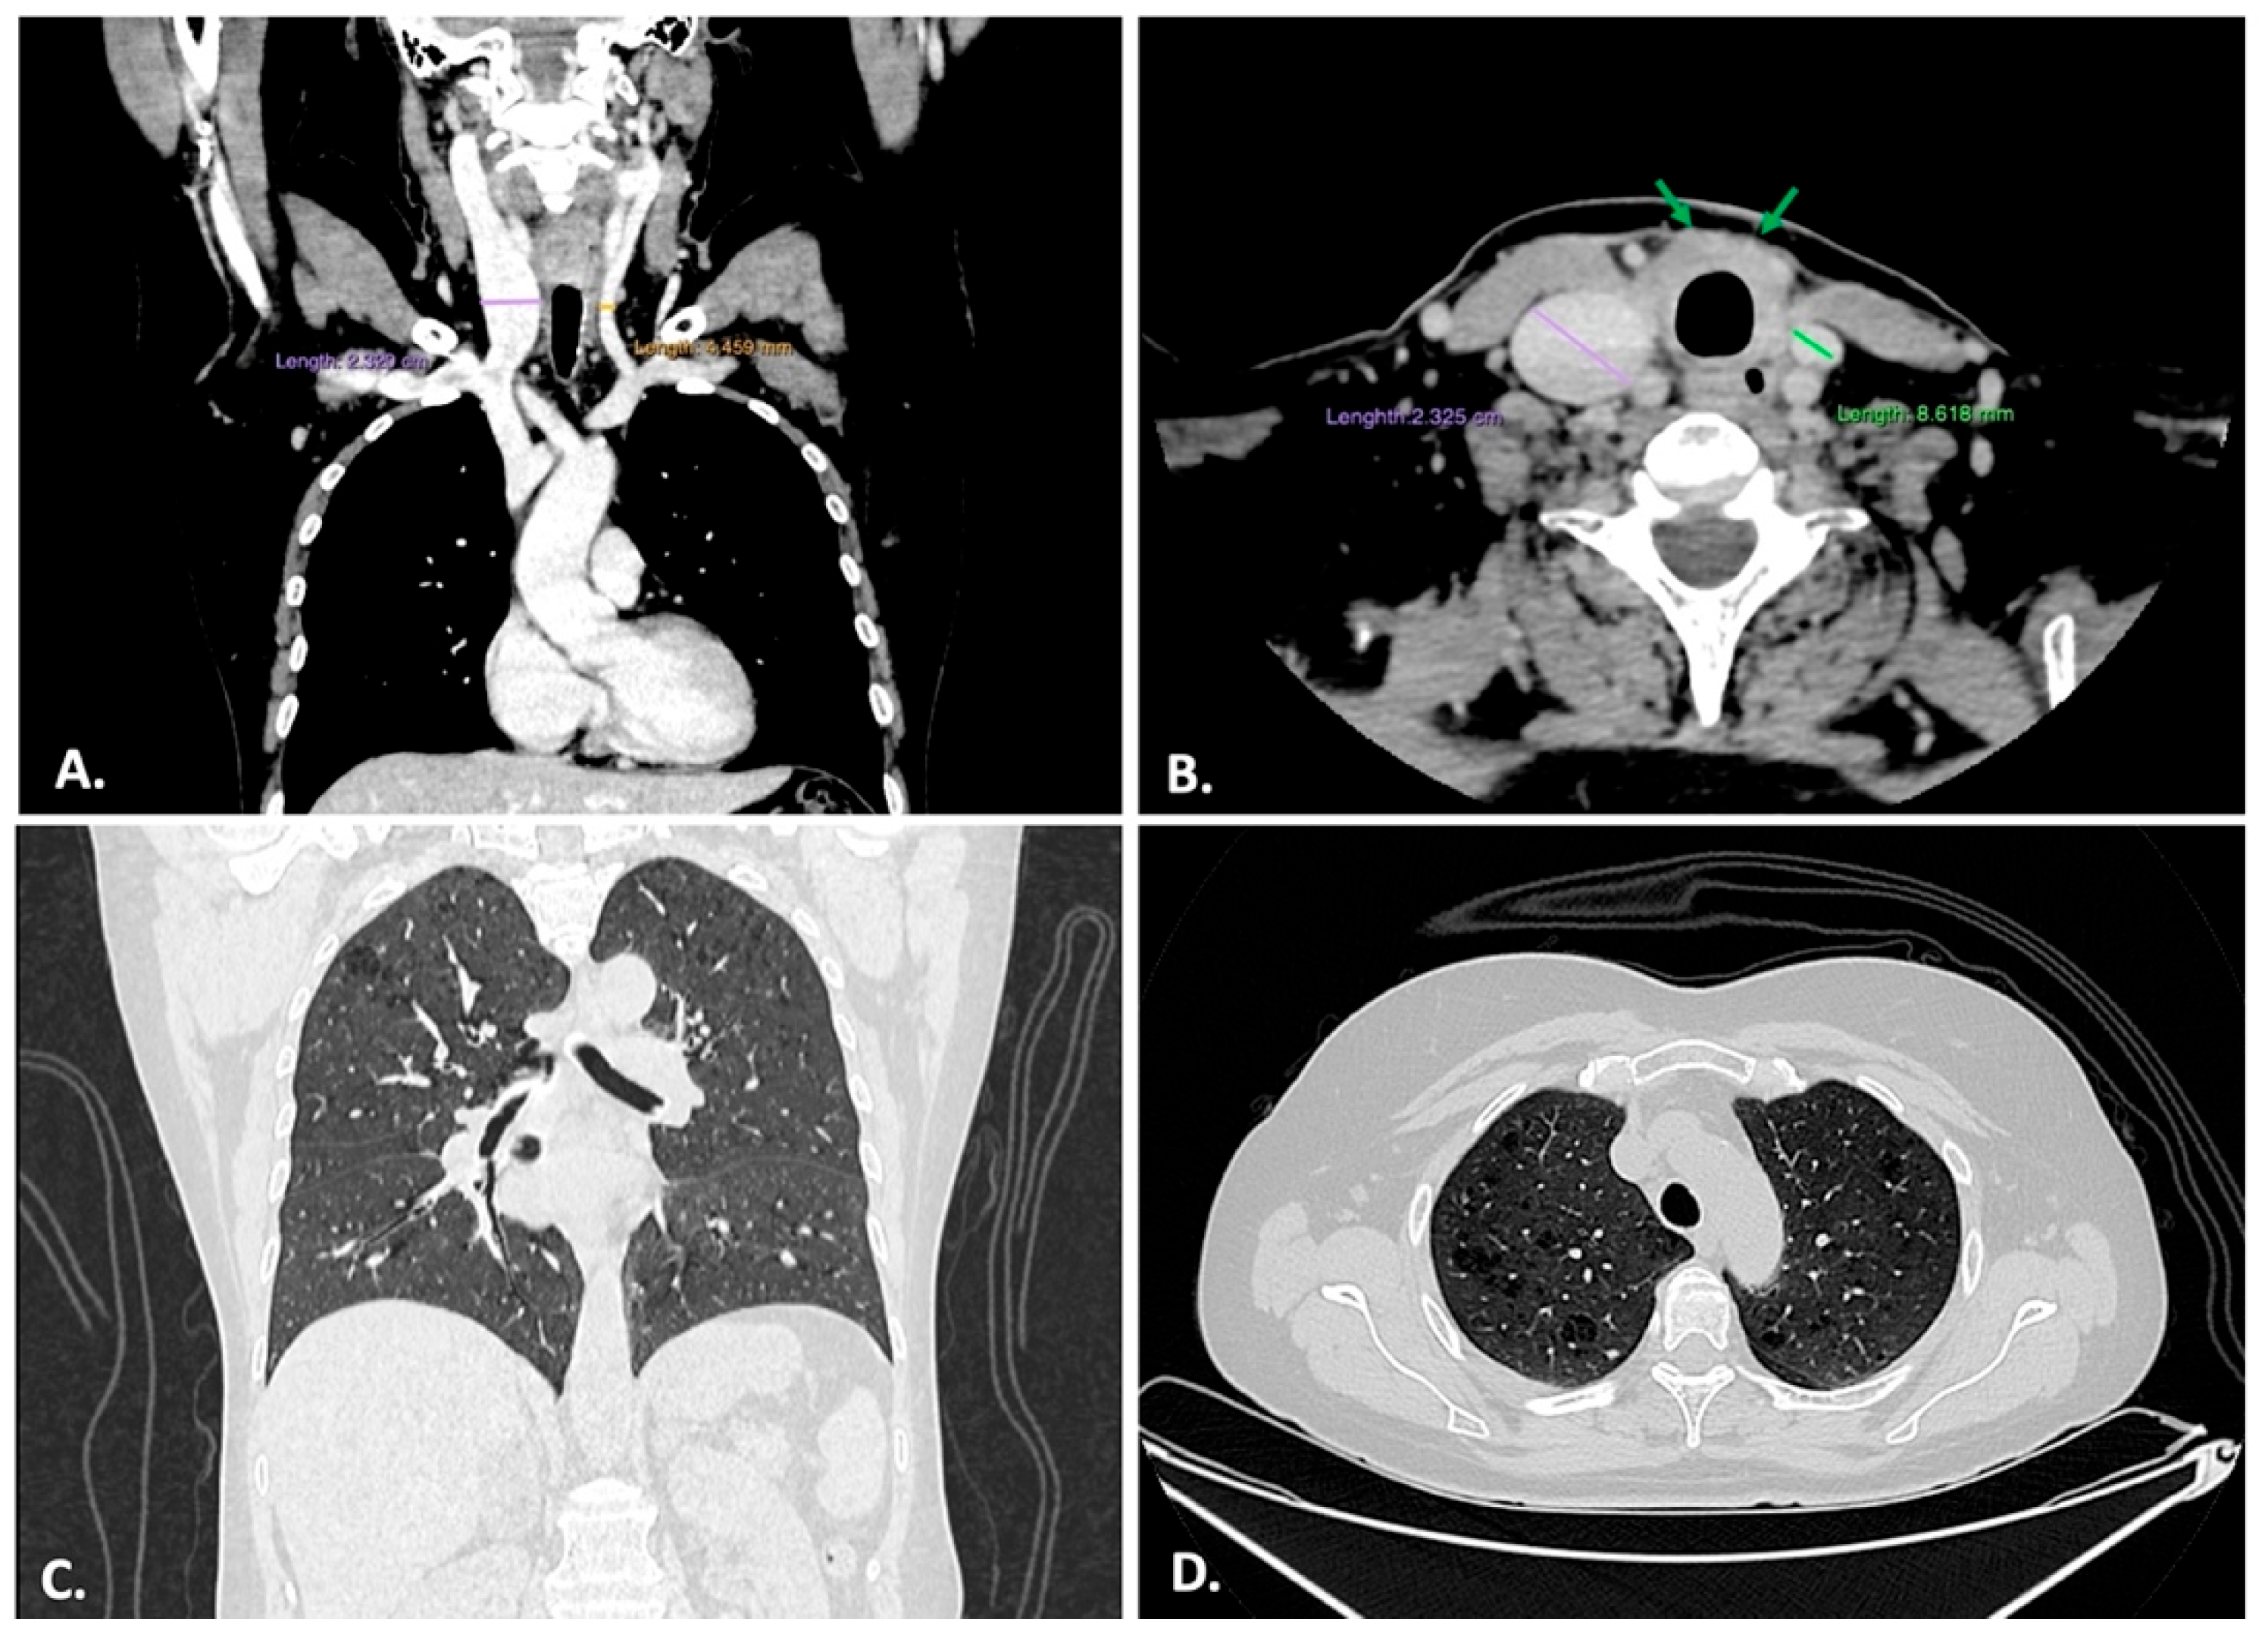

2.2. Imagistic Examination